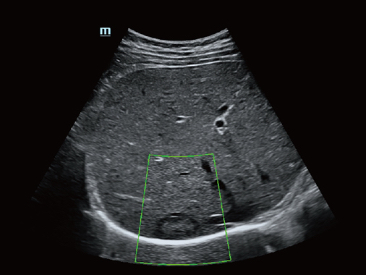

Od czasu kiedy zosta?a za?o?ona, Firma Mindray nieustannie poszukuje nowych sposob├│w na polepszenie precyzji w diagnostyce. Dzi?ki zastosowaniu najbardziej rewolucyjnej technologii ZONE Sonography? Technology, platforma ZST+ zastosowana w aparacie Resona 7 przenosi jako?? obrazu ultrasonograficznego na wy?szy poziom dzi?ki strefowemu uzyskiwaniu obrazu - zone acquisition i obr├│bkce danych kana?owych.

Oprócz uzyskiwania jako?ci obrazu typowego dla aparatów klasy premium, Resona 7 rozszerza mo?liwo?ci klinicznych badań USG dzi?ki rewolucyjnej funkcji V Flow, s?u??cej do oceny hemodynamiki naczyń, a tak?e najlepszej na rynku funkcji inteligentnego, automatycznego uzyskiwania p?aszczyzny na podstawie zestawów danych obj?to?ciowych 3D, umo?liwiaj?cej diagnozowanie stanu Centralnego Uk?adu Nerwowego u p?odu. Aparat Resona 7 ??czy w sobie najbardziej intuicyjn?, wielodotykow? obs?ug? za pomoc? gestów oraz wszystkie kluczowe funkcje kliniczne, co sprawia i? jest prawdziwym liderem we wprowadzaniu innowacji w ultrasonografii.